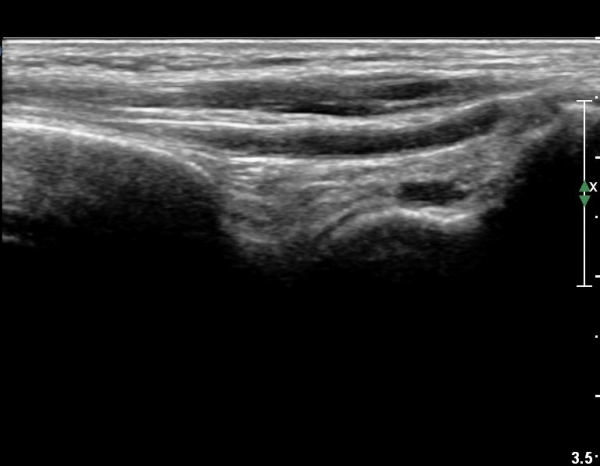

Àü¹æ¸»´ÜÁ¾°ñºñ°ñÀδë Á¾´Ü¸é°Ë»ç¿¡¼­ ƯÀÌ ¼Ò°ßÀ» º¸ÀÌÁö ¾ÊÀ½(»çÁø 1).